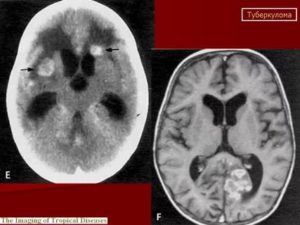

Это конгломератные казеозные очаги в веществе головного мозга, которые развиваются из глубоких бугорков, приобретенных во время недавнего или отдаленного периода бактериемии. Расположенные в центре активные поражения могут достигать больших размеров без появления признаков менингеального воспаления.

Воспалительный процесс образует области церебрита (инфильтрация мозговых тканей) или формирование абсцесса. Более типичное течение болезни – слияние казеозных очагов и фиброзной инкапсуляции (ТБ). На ранней стадии поражения односторонние, бесследно исчезают при медикаментозной терапии.